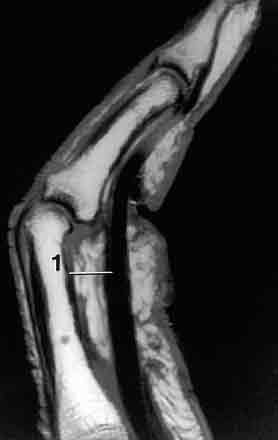

Zda se jedná o úplnou nebo neúplnou rupturu anebo jen natažení (přetažení, distenzi) musí být prokázáno dalšími vyšetřovacími metodami sonografie (přednostně – umožňuje vyšetření při pohybu), ideálně magnetické rezonance. (viz.obrazky)

MRI rekonstruované poutko